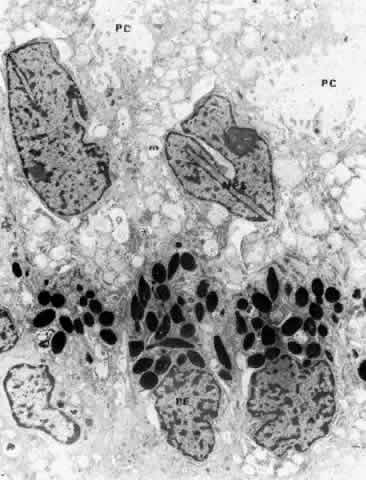

There are a large number of intercellular junctions between the ciliary epithelial cells, each giving important data about the specific functions of these cells (see Fig. 11). Toward the base of the NPE cells their lateral sides are joined by desmosomes (see Fig. 15). At their apical ends they are connected by typical tight junctional complexes consisting of a zonula occludens and zonula adherens (Fig. 19). These tight junctions represent the primary blood-aqueous barrier in the ciliary body. When large tracer molecules such as horseradish peroxidase are injected intravenously into primates,20,21 the tracer has an easy passage through the fenestrated capillaries of the ciliary processes, but does not pass beyond the apices of the NPE cells (see Fig. 19).

Fig. 19. Evidence of tight junctional complexes in the anterior ciliary epithelium of Macaca mulatta. The pigmented epithelial cells (PC) are outlined by a thin black line that is the reaction product of horeseradish peroxidase, a tracer substance injected intravenously in vivo. The tracer has entered the intercellular spaces of the nonpigmented epithelium (NPC) but is held up by occluding junctions (arrowheads), preventing further progress into the posterior chamber. (X 8450; Courtesy of Dr. Guiseppina Raviola)